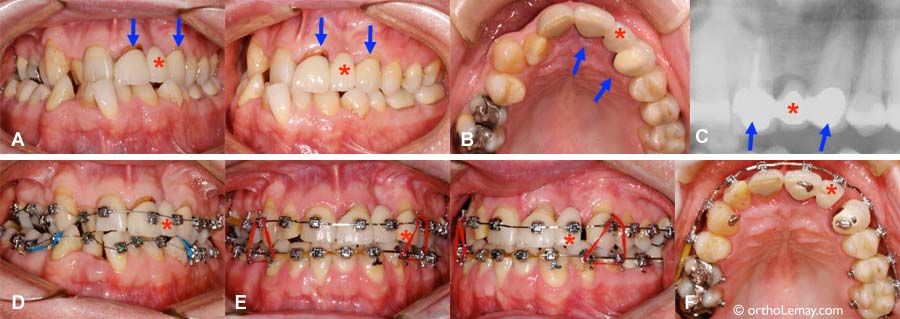

Sévère malocclusion avec déséquilibre des mâchoires, plusieurs dents manquantes et signes d’usure.

(A) Sévère malocclusion avec déséquilibre des mâchoires, plusieurs dents manquantes et signes d’usure. (B) Après l’orthodontie, la position des dents est adéquate mais il y a plusieurs espaces restants et des dents usées et inégales. Les flèches indiquent des implants dentaires qui ont été posés pour supporter des couronnes. (C) Après la phase restaurative où le dentiste a fait plusieurs facettes, couronnes sur implants et une prothèse partielle amovible inférieure.